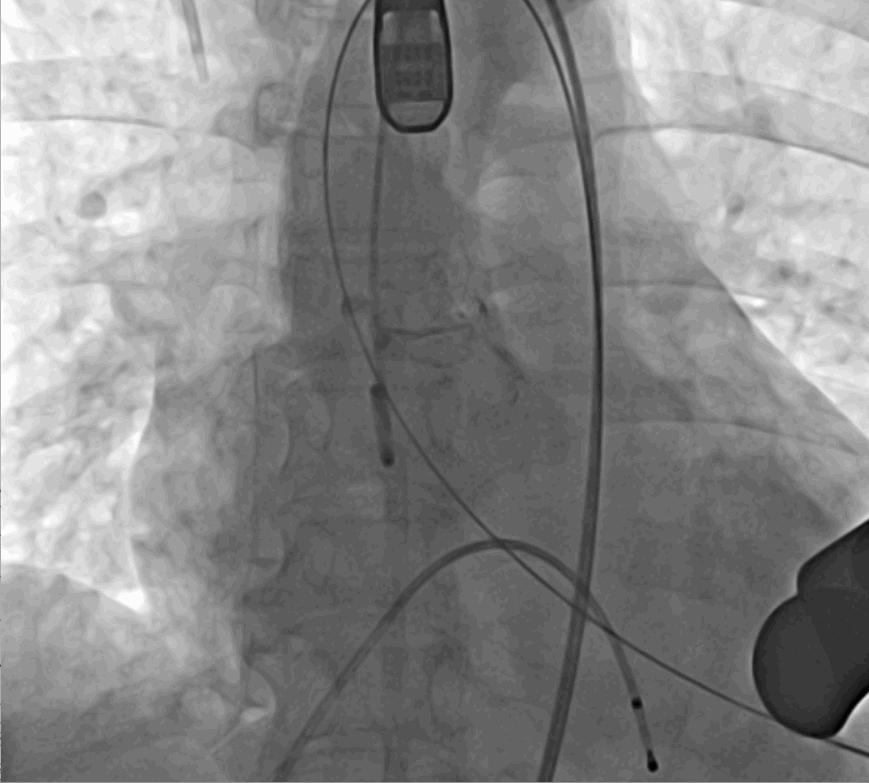

術(shù)前DSA影像圖